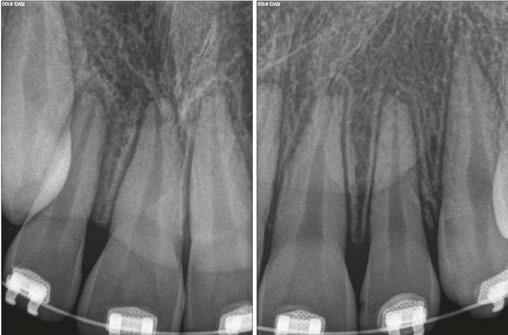

Luckily, the young boy was undergoing orthodontic treatment so the avulsed teeth remained in the oral cavity. As you can see from the clinical photograph in Figure 1, teeth Nos. 8, 9, and 10 would not have remained in the mouth if the orthodontic wire was not in place.

Two days after treatment, the patient was seen in my practice after the teeth were splinted back in place by the orthodontist. Figures 2A-2B are the preoperative radiographs after the teeth were reimplanted.

One can already appreciate the inflammatory resorption that is occurring at the apices of teeth Nos. 9 and 10. These images were taken just two days after the trauma.

Figure 1

Figures 2A-2B